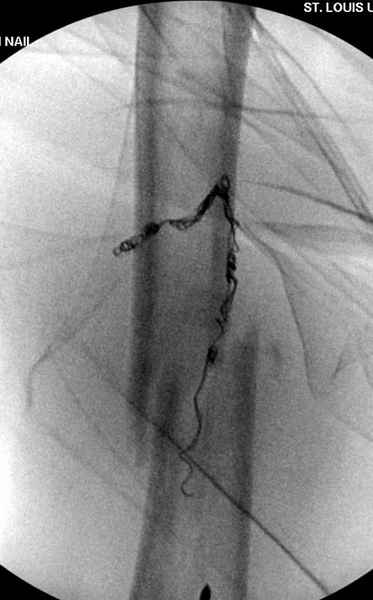

Для предупреждения кровотечения во время рассверливания, за день до операции провели эмболизацию сосудов питающий метастаз. http://radiology.rsnajnls.org/cgi/reprint/150/3/673.pdf (7-11, 12-15-16)